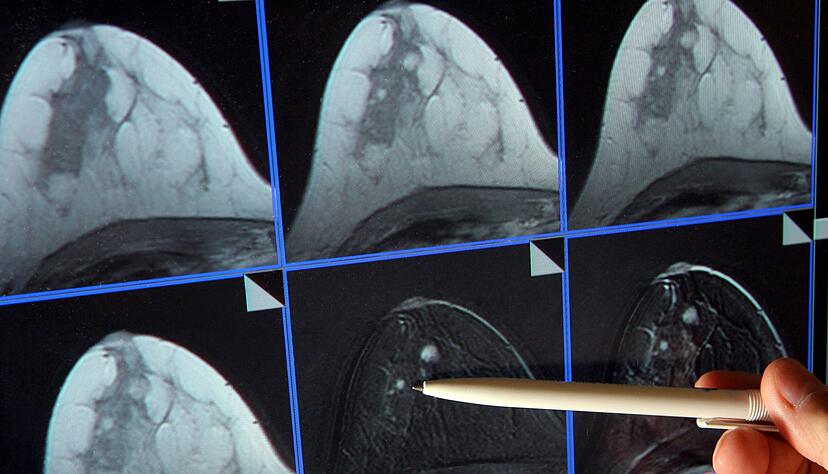

Kuhl ist überzeugt, dass sich die Zahl der an Brustkrebs sterbenden Frauen stark senken ließe. Dazu müsse die Früherkennung besser individuell angepasst werden. So sollten etwa Frauen mit sehr dichtem Brustgewebe, bei denen eine Mammografie nicht ausreicht, alternative Früherkennungsverfahren angeboten werden – insbesondere die Magnetresonanztomographie (MRT), für die es die höchste wissenschaftliche Evidenz gebe. Dieses Verfahren liefere umso bessere Nachweise, je aggressiver ein Karzinom sei.

MRT - bei vielen Frauen die weitaus bessere Wahl?

Etwa zehn Prozent der Frauen haben ein extrem dichtes Brustgewebe. Sie würden durch das derzeitige Mammografie-Screening unterversorgt, heißt es auch von der Europäischen Gesellschaft für Brustbildgebung (EUSOBI). Es gebe Nachweise, dass MRT-Untersuchungen die Brustkrebs-Sterblichkeit bei ihnen erheblich senken könne. Frauen sollten von ihren Ärzten generell über ihre Brustdichte informiert werden. Die Fachgesellschaft empfiehlt, Frauen im Alter von 50 bis 70 Jahren mit extrem dichter Brust alle zwei bis vier Jahre ein MRT-Screening anzubieten.